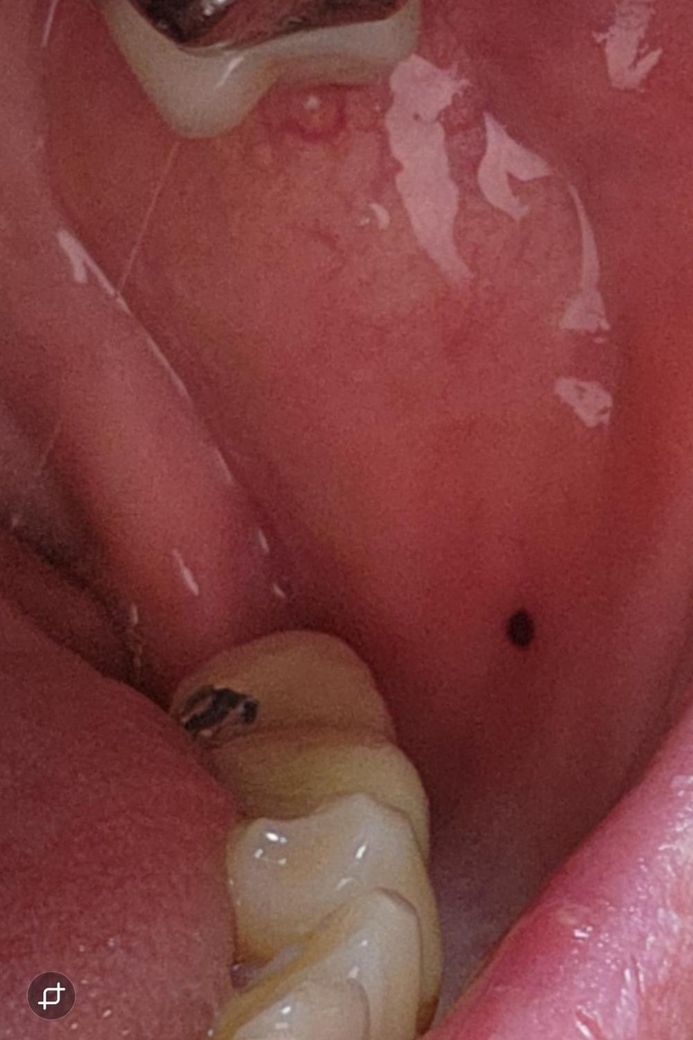

볼 안쪽 입안에 검은점이 생겼는데 큰병 일까요~? (도와주세요 ㅠㅠ)

다름이 아니라 오늘 양치하다가 우연히

볼 안쪽 입안에 양쪽으로 검은점이 2개 생긴걸 보게 되었는데 큰병 일까요~? ㅠㅠ..

• 1번 째 사진

• 2번 째 사진

-> 볼을 씹어서 혈종이 생긴 듯 합니다.

사진에 보이는건 볼살이 치아에 씹히면서 피가 뭉쳐서 생긴겁니다. 그냥 터트리면 괜찮아 지는겁니다.

사진으로 봤을 경우에는 혈종을 보입니다 점막조직에 손상이 가해지고 점막내부에 출혈이 되면 생기게 되는데 혀종은 자연적으로 없어지기 때문에 너무 걱정하지 않으셔도 됩니다.

자세한 확인을 위해서 치과에서 진료를 받아보는 것을 권유드립니다.

구강 내 흑색반(검은점)의 경우 흑색종으로 악성 종양화 될 가능성도 있으나 정확한건 검사를 해봐야 압니다 구강내과 가서 조직검사해보시기 바랍니다